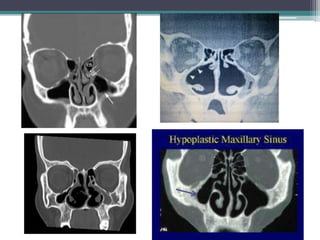

Radiological findings :

• Mucoperiosteal thickening of paranasal sinuses

• Loss of definition of osteomeatal complex

• Enlargement of nasal cavity with erosion and

bowing of the lateral nasal wall

• Atrophy of inferior and middle turbinates

• hypoplastic maxillary sinuses